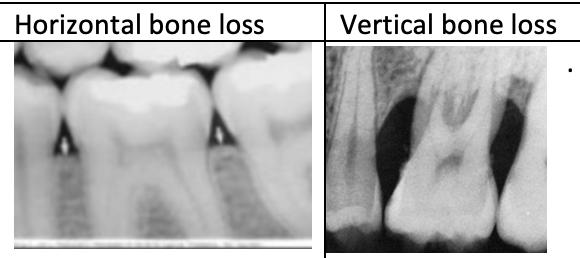

Explain the difference between horizontal and angular periodontal bone loss defects on a radiograph.

Horizontal bone loss- base of the pocket is located coronally to the alveolar crest.

Vertical bone loss-

Apical end of the pocket is located below the alveolar crest.